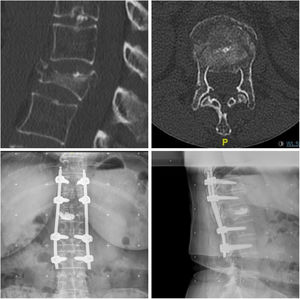

En los pacientes de menor edad y con menos comorbilidades se realiza abordaje retropleural/retroperitoneal MIS en decúbito lateral para corpectomía parcial de la vértebra fracturada y colocación de sustituto vertebral expansible siguiendo la técnica que realizan Bordon et al10; Este abordaje asocia menor número de complicaciones pulmonares en comparación con el abordaje transtorácico clásico. En el mismo acto quirúrgico, se cambia al paciente a decúbito prono para fijación posterior percutánea dos niveles por encima y dos por debajo (técnica 1) (fig. 2).

Mujer de 68 años con fractura de L1 tras caída de su propia altura. Se decide fijación percutánea T12-L2 y corpectomía retropleural con sustituto vertebral. Imagen de TC en cortes sagital y axial prequirúrgicos. Resultado radiográfico con proyecciones anteroposterior y lateral a los tres meses postquirúrgicos.